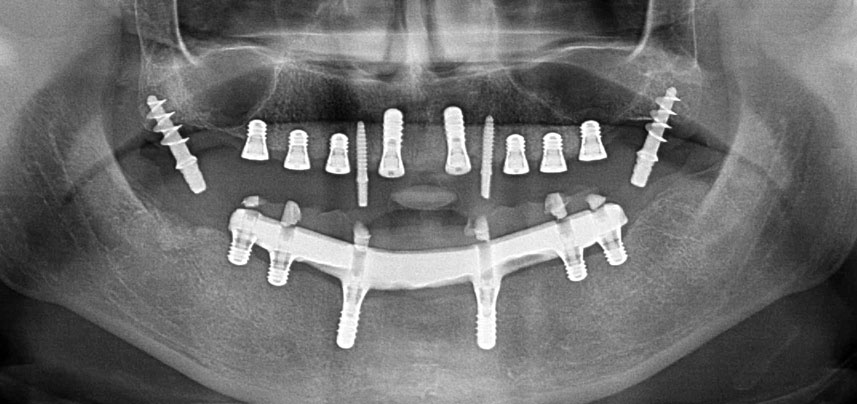

Постоперативна панорамна ренгенография

Фиг. 10 Постоперативна панорамна ренгенография показва всички импланти в подходящи позиции, включително временните птеригоидни импланти.